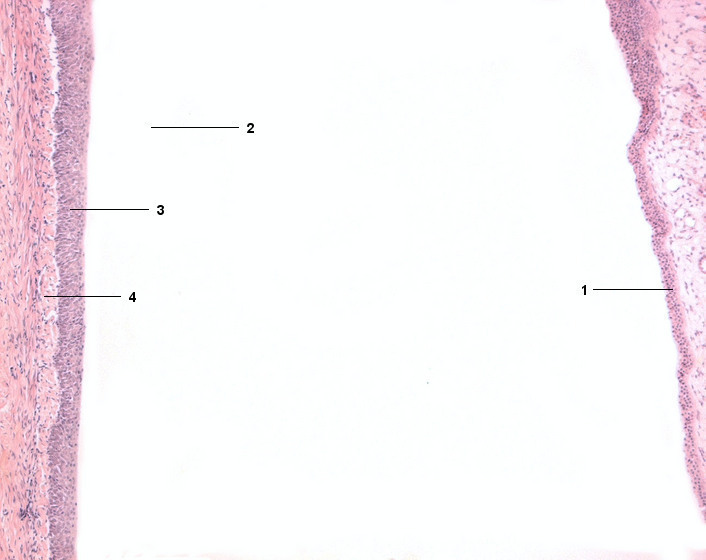

1 Papilla renalis (Nierenpapille), Epithel

2 Pelvis renalis (Nierenbecken)

3 Urothel (Übergangsepithel)

4 Lamina propria